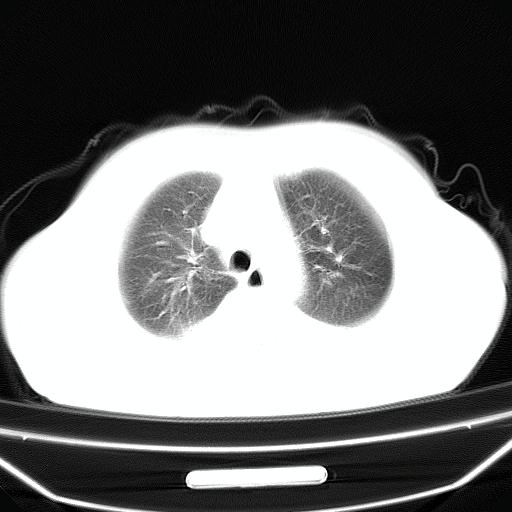

以下是引用jiangjing在2008-4-20 10:43:00的发言:[br]结合病史支持 冠心病[冠状动脉钙化],心功能不全,肺淤血、肺水肿,双侧胸腔与斜裂积液

以下是引用liuyue在2008-4-19 22:25:00的发言:[br]先考虑:1.心衰伴肺水肿、双侧胸腔积液、叶间积液、双下肺不完全性肺不张; [br] 2.冠状动脉粥样硬化。

以下是引用lijuanln在2008-4-19 23:05:00的发言:[br]两侧胸腔积液,肺水肿[br]心包积液[br]提示心衰